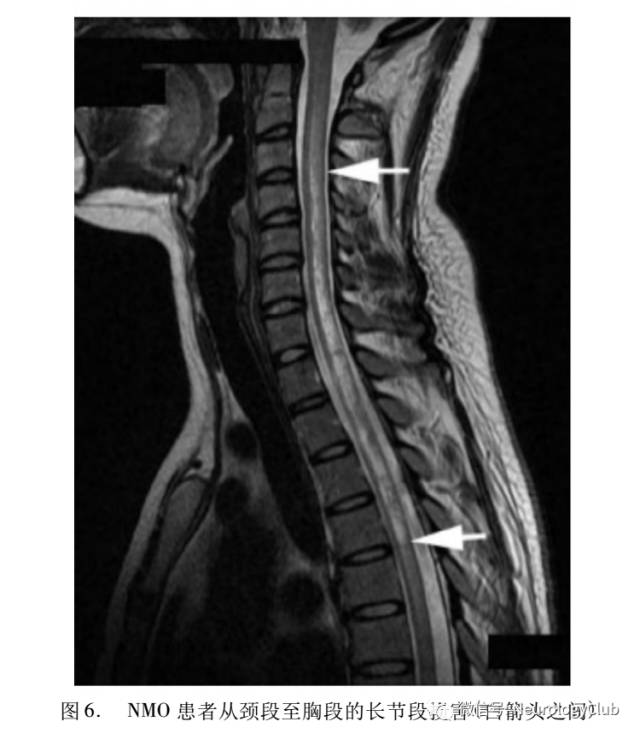

影像学检查是ON诊断及鉴别诊断中不可缺少的。ON急性期视神经信号异常、增粗、强化(图2)。MS高风险患者脑内还可见无临床症状的脱髓鞘病变(图3)。我们发现不典型ON患者视神经的异常信号与典型ON存在差异。NMO患者急性期脊髓出现超过3个节段的损害,病灶可强化(图6)。